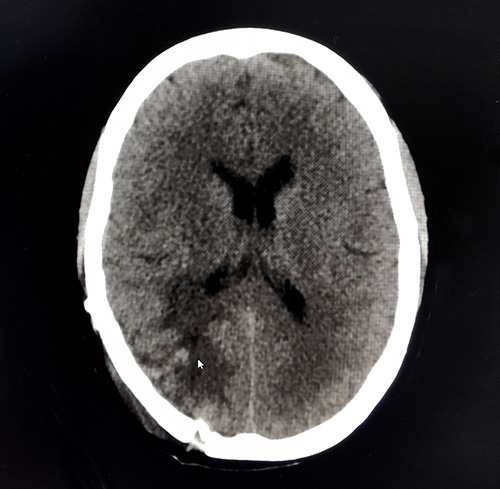

▲術后CT查片已不見腫瘤蹤跡

術后,胡女士恢復情況良好。沈教授表示,腦瘤的切除讓患者暫時脫離了險境,但仍存在復發(fā)的可能。后續(xù)通過積極采取化療、放療等多模式綜合治療,以此緩解臨床癥狀、減輕痛苦,從而達到患者生命延長、生活質(zhì)量得以顯著提高,所有這些還是可以做到的。